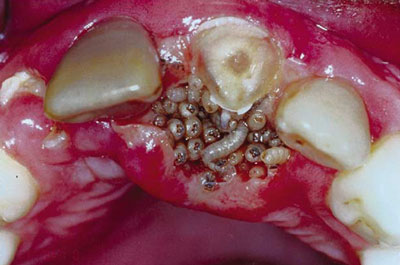

Após a penetração, começa a formar-se uma lesão nodular, avermelhada, com um orifício central, por onde é eliminada secreção aquosa, levemente amarelada ou sanguinolenta. Podem ser uma ou mais lesões e atingir qualquer área da pele, inclusive a boca.

Uma característica clínica que define o diagnóstico pode ser notada observando-se atentamente o orifício central da lesão. De tempos em tempos a larva sobe ao orifício para respirar e esta movimentação pode ser percebida claramente. Com a evolução, que pode durar entre 30 a 70 dias, a larva tende a deixar o orifício.

O diagnóstico dessa lesão é sempre clínico e o tratamento mais recomendado é a remoção mecânica das larvas, com irrigação com soro fisiológico e Tergentol a 10%.